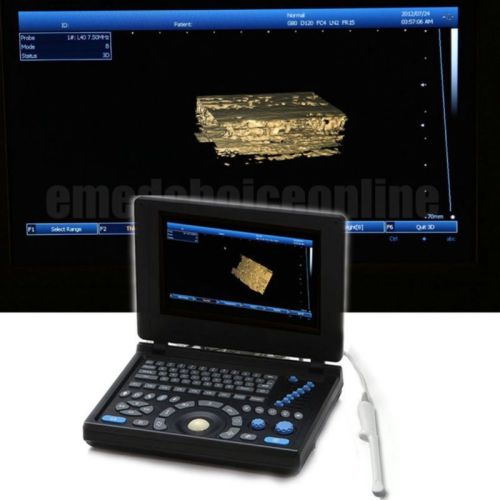

3D PC Platform Full Digital Laptop Ultrasound Scanner+ Convex &Linear BEST CHOIC

HOT HOT HOT! Digital Ultrasound Scanner 4-frequency Convex +Linear probes +3D

3D Digital Ultrasound Scanner +Convex TV 2 probes Optional 2 probes+3 years warr

ONLY 1-MONTH SALE!!! Digital Laptop Ultrasound Scanner Diagnostic + Linear 3D

NEW Full Digital TFT LCD Ultrasound Scanner High-resolution (built-in 3D) CONVEX

FULL DIGITAL Portable Ultrasound Scanner 3 probes "Convex,Linear,TV" +3D GOOD+++

3D Full-digital Ultrasound scanner machine with 3.5MHz R60 convex +2 USB Ports

Hot 3D Full-digital Ultrasound scanner machine W CONVEX +2 connectors+2USB ports

3D 10.1" Full Digital Laptop Ultrasound Scanner Machine +Micro-convex Probe CE

in 3D Full Digital Laptop Ultrasound Scanner (PC) with convex probe Free Ship

NEW 10.4" 3D PC platform Full Digital Laptop Ultrasound Scanner+ 3.5Convex Probe

+Aluminum box Full Digital 3D PC LAPTOP Ultrasound Scanner vaginal NEW